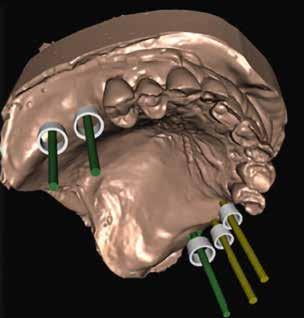

Egy teljesen digitális protetikai munkafolyamat

Az implantáció egy biztonságos és megbízható módszer a hiányzó fogak pótlására. Az elmúlt néhány évben az implantológia jelentős fejlődésen ment át a bioanyagok, a kezelési technikák, illetve a kapcsolódó fogászati eszközök terén. Az implantológia digitalizációja is kiemelkedő előrelépéseket mutat. A fogorvos már a műtét elvégzése előtt képes előre megtervezni

és vizualizálni a kívánt eredményt, ezáltal hatékonyabb az orvos–páciens közötti kommunikáció, illetve a páciens könynyebben dönt a kezelés mellett. A kiszámíthatóság javításának másik szempontja, hogy a kezelés tervezése során kiemelt jelentőséget tulajdonítsunk a lágyszöveteknek. Az implantátumbeültetés hosszú távú sikere számos tényezőtől függ, többek között az implantátum körüli szövetek egészségétől. Mindent meg kell tenni a megfelelő implantátum körüli zárás érdekében. A következő esetleírás a lágyszövetmenedzsment és a teljesen digitális protetikai munkafolyamat kombinációját mutatja be 4-es típusú implantátumbeültetés során.

Egy fiatal páciens jelentkezett nálunk, akinek eltörött a szabad véggel rendelkező hídja (1. ábra). A hiányzó, első premoláris fog esetén implantációs pótlást javasoltunk. A csontállomány értékeléséhez CBCT-vizsgálatot végeztünk, és az elemzéséhez NNT Viewert (NewTom) használtunk, és copaSKY 4×10 mm-es (bredent medical) implantátumot választottuk a fog pótlásához

(2. ábra). A lágyszövetek értékelése Seibert szerinti I. osztályú csontdefektust állapított meg (3. ábra), ezért a beavatkozáskor palatinális „tekercslebenyt” preparáltunk (palatal roll flap), és implantációt végeztünk, hogy kompenzálni tudjuk a bukkális lágyszövet-behúzódást. Megmértük a vertikális lágyszövetvastagságot, és úgy terveztük, hogy a szubkresztális implantátum beültetése összhangban legyen a biológiai szélesség kialakulásával a transzgingivális gyógyulási periódus alatt (4. ábra)